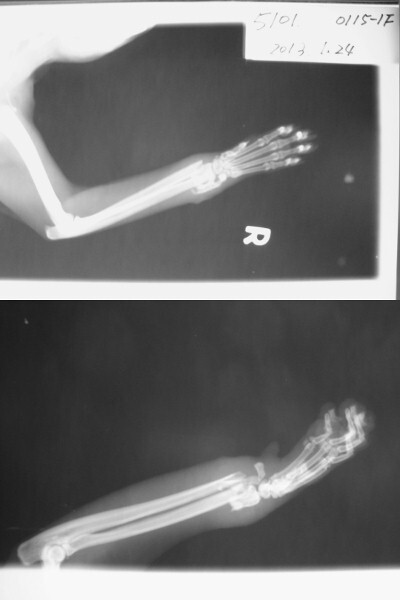

主題: 高雄 鳳山區 五福一路 老鼠夾貓咪 申請者姓名: 劉雅雲 花色: 申請日期: 2013-03-01 09:58:05 申請者部落格: 申請者臉書網址: 所在縣市/合作醫院: 高雄市/樂生動物醫院 治療費用: 18300元 需求人數: 19人 已結案 (2013-06-27 14:21:29) 報名人員: Yi-Jing Wang(已付款)、Luna Tsai(已付款)、Phyllis Chan(已付款)、雲之凡 x2(已付款)、Ray Chen(已付款)、Cay Way(已付款)、Li Li Hsieh(已付款)、王鼎方 x2、betty huang(已付款)、KAYU、謝欣蓓(已付款)、謝立立(已付款)、以四面佛名義迴向阿咪、咪仔 x5(已付款)、chiawei(已付款)、Emily Chou x2(已付款)、 候補人員: 動物病情說明: 1/15志工版裡的求援案件,被老鼠夾夾到的貓咪在地方拖行, 被好幾位民眾合力打開老鼠夾之後貓咪緊張躲到二樓的遮陽棚快4天沒下來吃東西, 後來到民眾二樓開窗去放誘捕籠抓到貓咪就醫. 醫生到院幫貓咪拍X光, 因為有骨折, 採用內固定法手術, 貓咪到院因為已經有化膿,所以留至院中治療, 恢復時間會較長.

明細如下:

血液生化及電解質 1500

X光片 300*6 = 1800

內固定法手術 6000

住院治療 300*30=9000<1/15 - 2/27> 醫生只算30天費用

Total: 18300